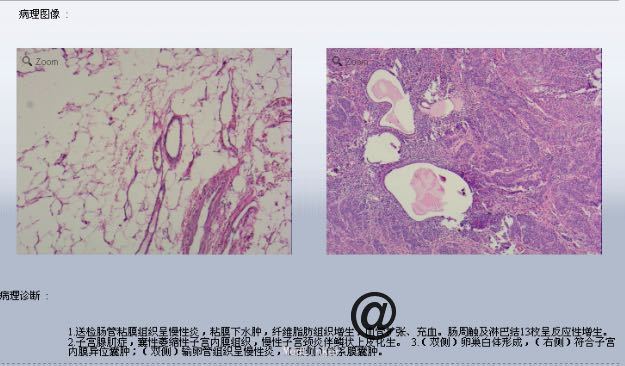

请妇科会诊,该科医师行妇检未见明显包块,且CA125正常,建议行小肠检查,同时行彩超探查了解包块来源,妇科彩超:子宫较小,宫体后壁肌壁间肌瘤(稍凸向宫腔),右侧附件区实质性包块,考虑为右侧卵巢肿瘤,左侧附件区未见明显异常显示,盆腔未见明显积液。 请妇科商议并于患者沟通后于2015.10.08转入妇科,转科行积极完善术前准备,于10.16行剖腹探查术。术中见:子宫稍大,质硬,后壁与直肠致密粘连,左侧卵巢大小正常,右侧卵巢增大直径约4cm,双侧附件与子宫后壁及盆壁致密粘连,分离盆腔粘连后可见巧克力样液体,阑尾可见约9*5*4cm肿瘤,包膜完整,与周围组织无粘连。请胃肠外科主任上台会诊,行阑尾切除术,术中快速病理切片检查示:(阑尾)腺上皮高级别上皮内瘤变(腺上皮中-重度异型增生),确诊待常规。再次向家属交代病情,将快切结果告知患者家属,患者家属了解病情,要求切除右半结肠,切除全子宫及双侧附件,最终行:全麻插管下行右半结肠根治性切除+肠粘连松解+腹式全子宫切除+双侧卵巢输卵管切除术。术后病检提示:(阑尾)中分化腺癌,癌浸润达肌层。阑尾手术切缘未见癌组织。免疫组化:CK19(+),Ki-67 LI约60%。子宫附件及右半结肠:1.送检肠管粘膜组织呈慢性炎,粘膜下水肿,纤维脂肪组织增生,血管扩张、充血。肠周触及淋巴结13枚呈反应性增生。 2.子宫腺肌症,囊性萎缩性子宫内膜组织,慢性子宫颈炎伴鳞状上皮化生。 3.(双侧)卵巢白体形成,(右侧)符合子宫内膜异位囊肿;(双侧)输卵管组织呈慢性炎,(右侧)伴系膜囊肿。